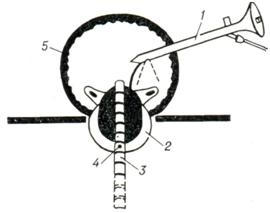

С 1964 г. значительное распространение получает метод криохирургии предстательной железы. С помощью специального инструмента замораживают предстательную железу, содержащую аденоматозные или раковые узлы (рис. 15).

Наиболее широко применяется криотермический прибор Linde СЕ-4 cryosurgery system. Основной частью его является специальный криозонд, смонтированный в виде катетера № 25 по Шаррьеру, в котором циркулирует жидкий азот. Рабочая замораживающая поверхность соответствует простатической части мочеиспускательного канала, а нерабочая изолирована таким образом, что опасность замерзания других отделов мочеиспускательного канала и мочевого пузыря надежно устранена. Криодеструкция обычно происходит при t° от —120 до —190° в течение 2 — 5 мин.

После применения холода в течение 2 суток развивается стадия острого отека. Затем в течение недели— стадия коагуляционного некроза с аутолизом клеток, а затем стадия заживления— от 3 до 6 месяцев.

Учитывая, что основным недостатком криозондов является невозможность применения их под контролем зрения, Рейтер (Н. J. Reuter) предложил проводить визуальный контроль с помощью особого цистоскопа-трокара, вводимого в мочевой пузырь путем надлобковой пункции.

Криохирургическая операция показана тяжелобольным, которым противопоказана аденомэктомия или трансуретральная резекция (пример¬но 5 —10% случаев). При криохирургии простаты могут быть осложнения: поздние кровотечения, пиелонефрит, свищи мочеиспускательного канала, остеит лобковых костей.